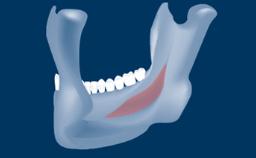

- intraoperative complications of transcrestal sinus floor elevation